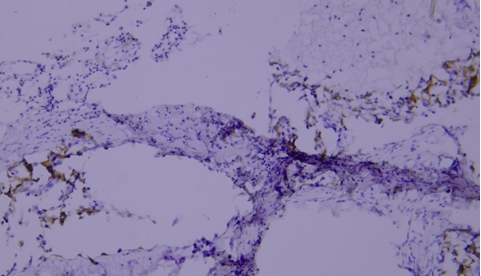

典型实例:人前列腺石蜡组织切片TIMP-1染色,因干片出现假阴性(黑色箭头区域)。

解决建议:使用加入Tween-20的缓冲液,可有效防止切片干燥。